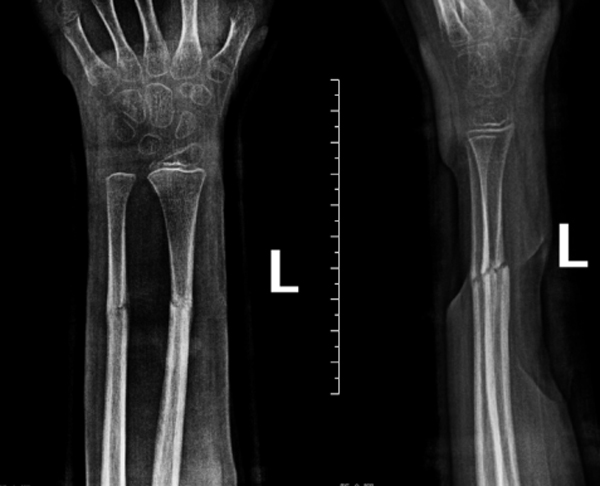

复位后,医护团队为家属详细指导护理事项,并制定系统复查计划。在随后数周的跟踪随访中,患儿骨折位置维持稳定,未出现移位。直至拆除夹板之日,其左前臂功能已基本恢复,骨骼愈合近乎完美。

复位后X光复查